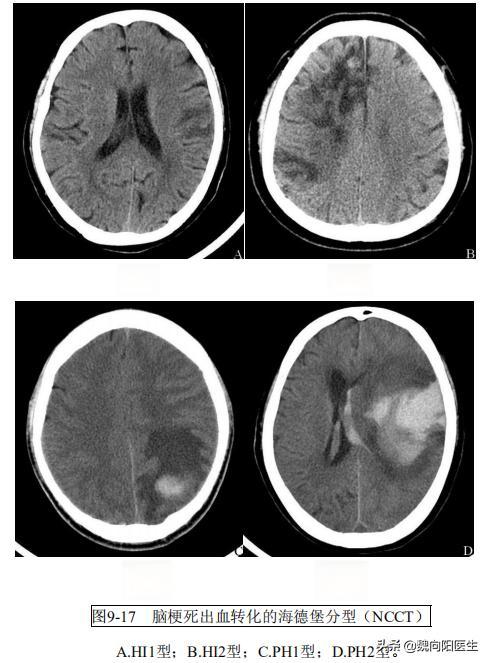

这种现象被称为“出血性脑梗死”,是指在缺血性脑梗死的基础上,由于缺血区的脑组织重新恢复血流灌注,导致梗死区域内出现继发性出血。根据与治疗的相关性,出血性脑梗死可分为自发性和继发性两种。自发性出血性脑梗死是指未使用溶栓、抗凝等增加出血风险的治疗方法而发生的出血;继发性则是指在使用这些治疗方法后发生的出血。

脑梗后脑出血的发生率并不低。文献数据显示,自发性出血性脑梗死的总发生率约为7% 2[出血性脑梗死的总发生率约为7% 29%](wxb://marking)1% 2%。而静脉溶栓后出血性脑梗死的总发生率更高,约为10% 48%,其中症状性出血性脑梗死的发生率为2%~7%。